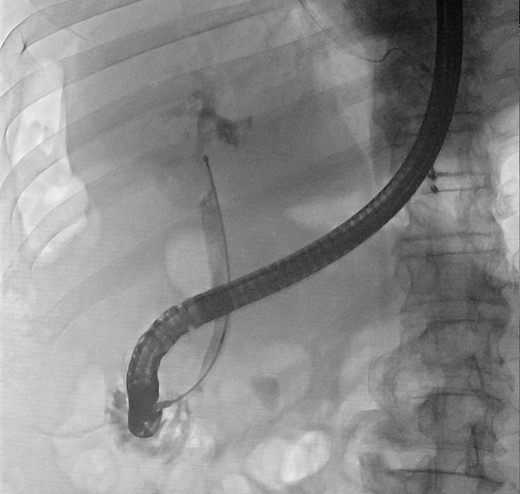

In view of his multiple medical comorbidities, which included obesity, hypertension, hyperlipidemia, ischemic heart disease with history of percutaneous transluminal coronary angioplasty, obstructive sleep apnea and sick sinus syndrome, he was considered a poor candidate for definitive surgery. Therefore, after the index cholangitic episode had settled, he received further endoscopic treatment. A combination of endoscopic papillotomy, biliary stenting and mechanical lithotripsy (ML) was adopted. After a total of eight additional sessions of ERCP, with repeated stent exchange, stone clearance was achieved. He was well and discharged with cleared ducts. Long-term stenting was not required.